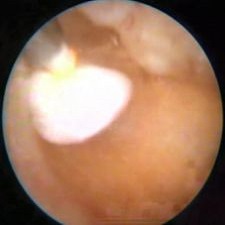

Nejčastější hysteroskopické nálezy

Odstranění reziduí po porodu nebo potratuOdstranění

Odstranění většího polypu či myomuOdstranění